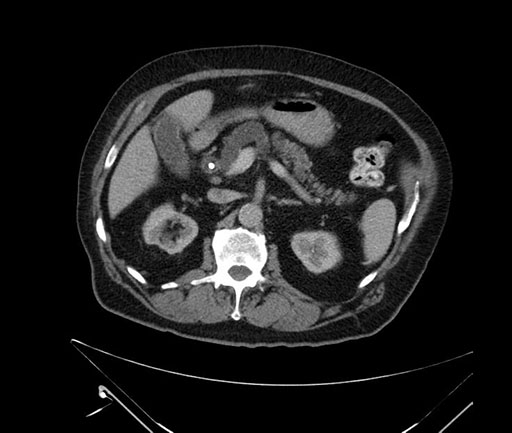

Axial - 3 months prior